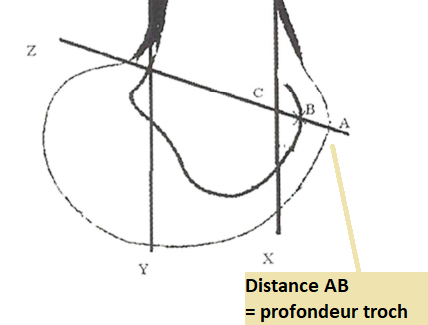

Profondeur trochléenne

- Normal >5mm